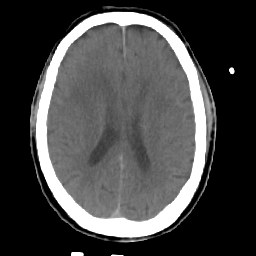

Meningioma: Roentgen-ray CT #2 -- Slice #12

[Home][Help][Clinical] Slice 12